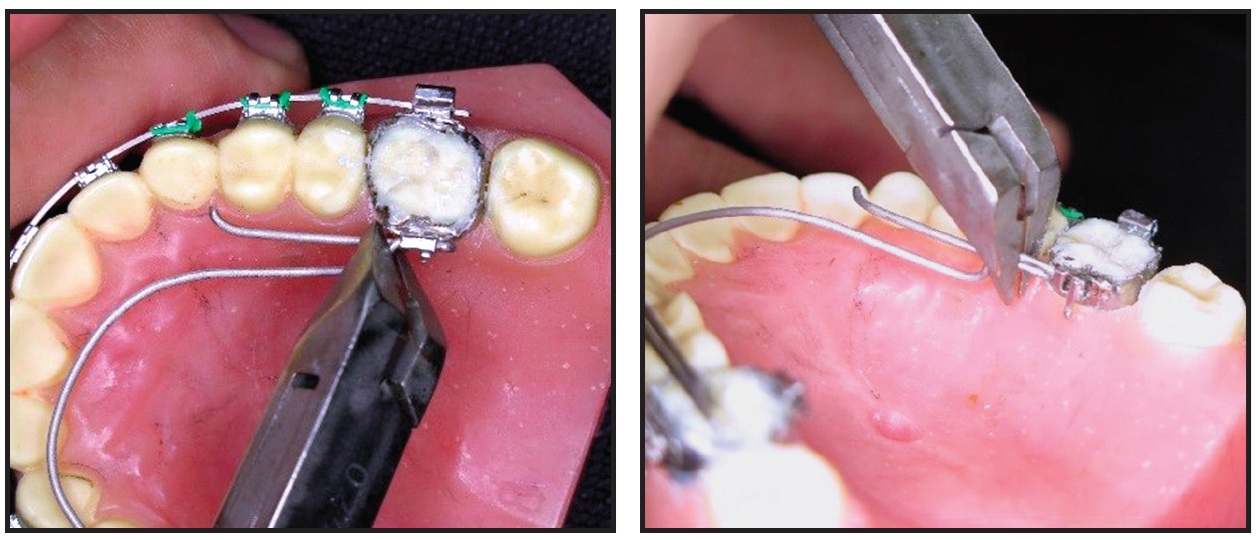

The non-helix is easily detached from the lingual sheath by engaging an angled ligature cutter and rotating it against the mesial aspect of the molar (Fig. 4). Adjustments take about five to 10 minutes. The non-helix is then replaced with a “click” using a lingual arch plier.

Fig. 4 Appliance removed from lingual sheath by engaging angled ligature cutter and rotating it against mesial aspect of molar.